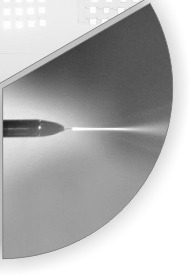

"MR-HIFU-Pancreas" project aims to develop MR-guided HIFU for treatment of pancreatic cancer.

Soluxx develops MR-compatible measurement equipment and electronics.